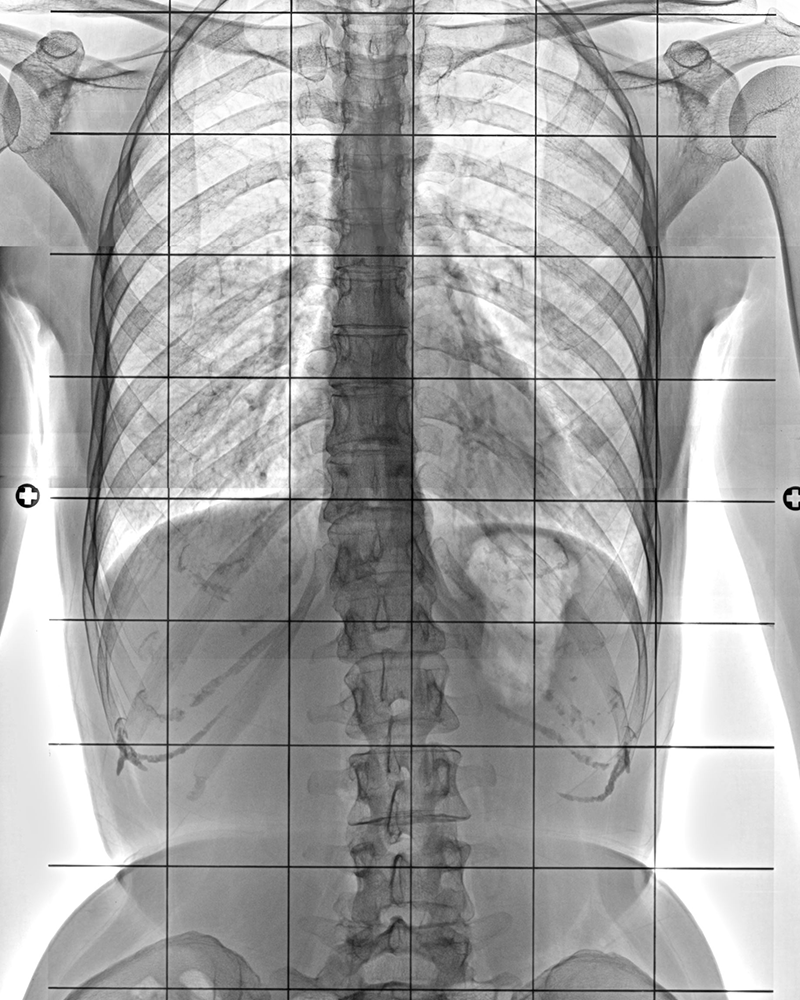

고난이도 척추수술이란?

10mm 이하의 피부 절개를 통해 좁아진 척추관을 넓혀 줌으로써 협착증이나 디스크에 의한 신경압박을 해소해주는 치료입니다. 수술 후 약 1~2일 후 퇴원 가능하며 이후 허리 통증이 완화됩니다.